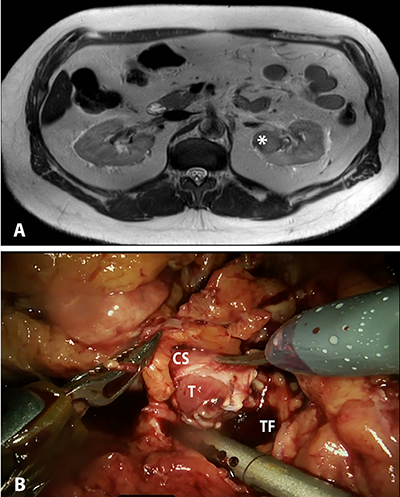

We present a 62-year-old man with a

cm left upper pole renal mass (Figure 1

A). The mass was mostly endophytic, though still present at the

cortico-medullary junction, so RCC and urothelial carcinoma (UC) were both

potential diagnoses.

Left retrograde pyelogram and ureteroscopy

performed one month prior to definitive surgery were normal, and selective

cytology and brush biopsy were both negative for malignant cells. Chest CT was

negative for metastatic disease. Given this workup, robotic partial nephrectomy

(RPN) was performed for presumed endophytic RCC.

The kidney was fully mobilized and the

main renal artery was clamped, then extirpation was attempted. However, upon

entering the collecting system, the tumor was found to be inside the lumen (Figure 1 B). The immediate concern was

for UC, and the procedure was converted to a nephroureterectomy. The patient recovered from surgery and was

discharged from the hospital on post-operative day two.

Figure 1. A,

Magnetic resonance imaging (MRI) showing endophytic, posterior upper pole left

renal mass (indicated by *), suspicious for carcinoma. B,

Intraoperative photograph showing grossly invasive mass involving the lumen of

the collecting system. T – Tumor; CS –

collecting system; TF – tumor fossa.